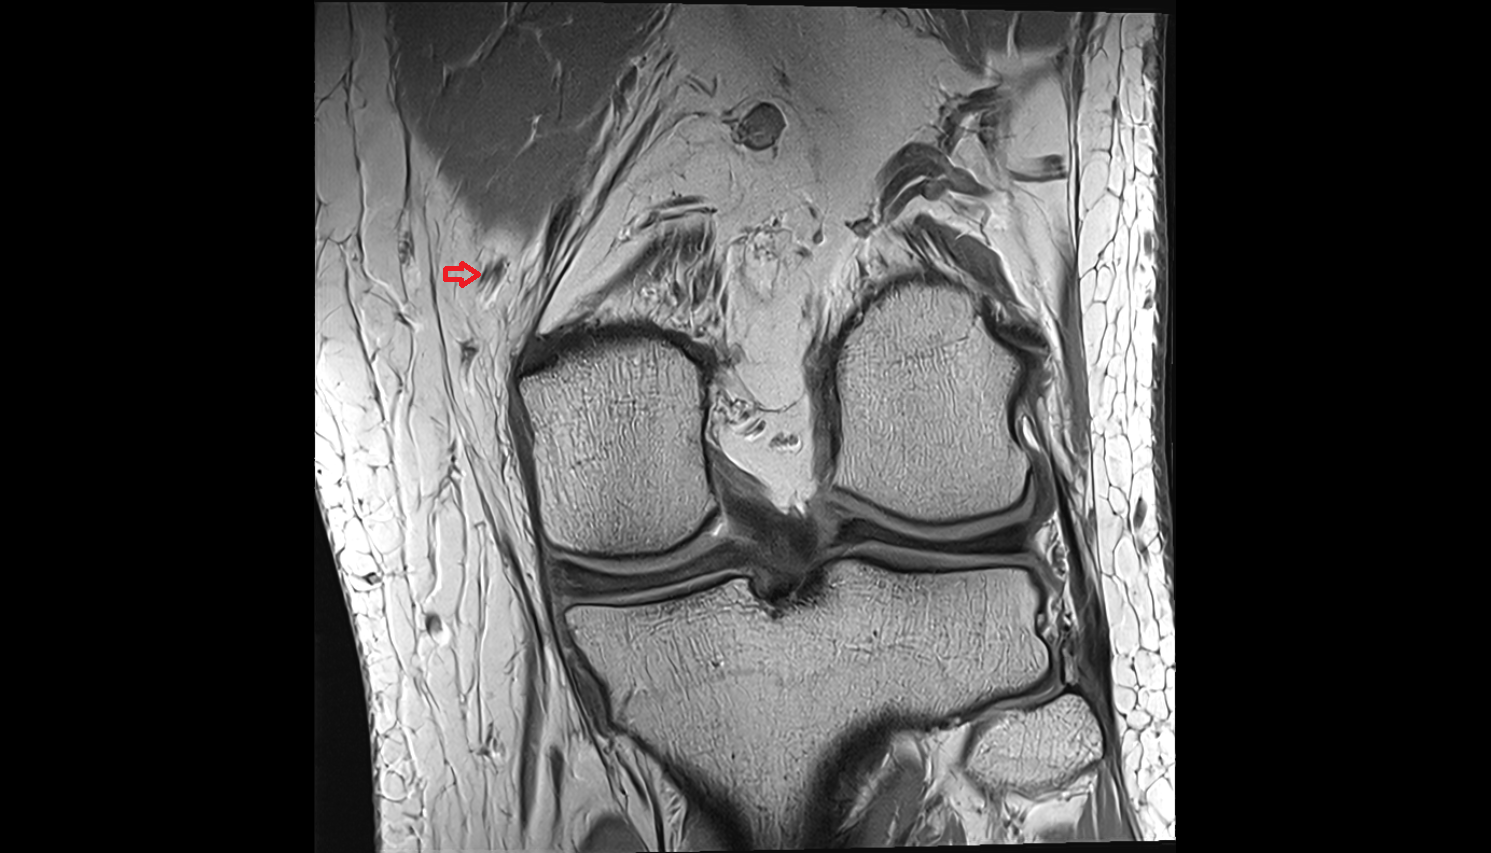

- Medial collateral ligament

- Lateral collateral ligament

- Medial epicondyle of femur

- Lateral epicondyle of femur

- Knee Joint